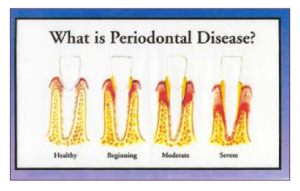

Probiotics have grown in popularity over the last few years. First, as a helpful ingredient for digestive health, now they are showing promising attributes to your oral health. From new mouthwashes and gums, probiotics are being focused and improved to help prevent cavities and bad breath, along with keeping gingivitis at bay. Over half of American adults have had or currently suffer from periodontal disease, also known as gum disease. There are many ways, however, that you can rebuild your gums including proper oral care and eating the right kinds of foods.

Over half of American adults have had or currently suffer from periodontal disease, also known as gum disease. There are many ways, however, that you can rebuild your gums including proper oral care and eating the right kinds of foods. When it comes to any kind of oral discomfort, there are always many potential reasons for the pain. However, almost always, the pain can be determined as an issue with the teeth, gums, or tongue. When specified to those three, you can narrow down the possible causes of the pain.

To keep a healthy smile, one must focus on the gums just as much as their teeth. Without proper care, gums can harbor many harmful types of bacteria that can result in gum disease. We already listed the best ways for  When people think of dental hygiene, they often only focus on the teeth. That's what most people see, right? Bright, white, straight teeth are the goal. However, most people neglect to consider how important it is to take care of your gums properly. While sore, sensitive gums can occur from lack of brushing and proper care, the gum's biggest threat is Periodontal Disease, or Gum Disease. According to the National Institute of Dental and Craniofacial Research, over

When people think of dental hygiene, they often only focus on the teeth. That's what most people see, right? Bright, white, straight teeth are the goal. However, most people neglect to consider how important it is to take care of your gums properly. While sore, sensitive gums can occur from lack of brushing and proper care, the gum's biggest threat is Periodontal Disease, or Gum Disease. According to the National Institute of Dental and Craniofacial Research, over